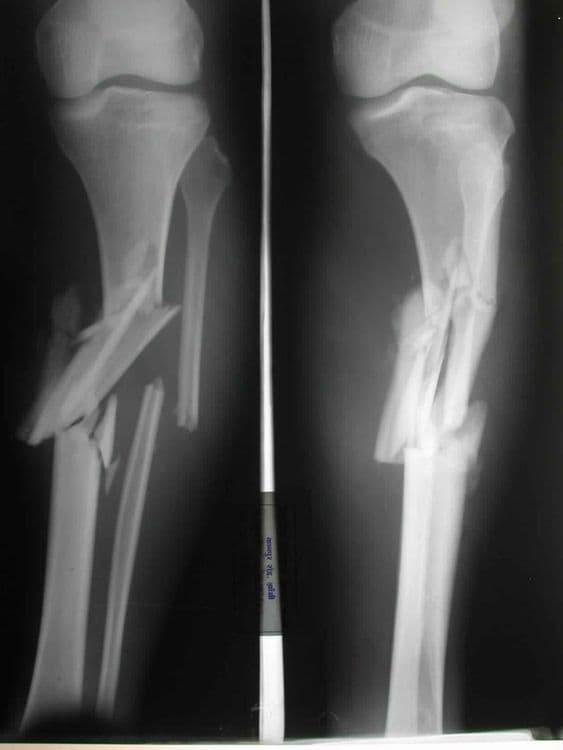

Comminuted Fracture - हाडांचा पूर्णतः चुरा होणे.

Oblique Fracture - हाडाच्या अक्षावर झालेले फ्रॅक्चर.

Transverse Fracture - हाडाचा सरळ सरळ मध्यभागातून तुकडा पडणे.